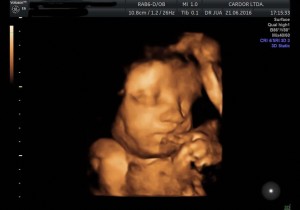

El desarrollo del feto varía en cada trimestre del embarazo.

A partir del segundo trimestre de embarazo, entre las semanas 13 y 27, sus órganos van madurando y adquieren mayor complejidad.

Vea la siguiente presentación. Imágenes 100% Cardor: